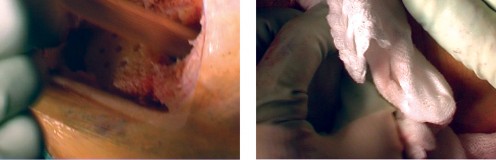

The most ubiquitous approach for TKA is the medial parapatellar arthrotomy. A straight, anterior longitudinal skin incision is made, extending from just proximal to the superior pole of the patella to just medial to the tibial tubercle. Full-thickness fasciocutaneous flaps are elevated to preserve the subdermal vascular plexus. The arthrotomy is then initiated through the medial retinaculum, coursing proximally into the quadriceps tendon (leaving a small medial cuff for later repair) and distally along the medial border of the patella and patellar tendon.

Once the joint is entered, the patella is either everted laterally or laterally subluxated, depending on the surgeon's preference and the stiffness of the extensor mechanism. A meticulous synovectomy and excision of the infrapatellar fat pad (Hoffa's fat pad) are performed to enhance visualization of the lateral compartment and the tibial plateau. All peripheral osteophytes on the femur and tibia must be aggressively resected at this stage. Retained osteophytes will artificially tension the collateral ligaments, leading to erroneous gap balancing and postoperative stiffness.